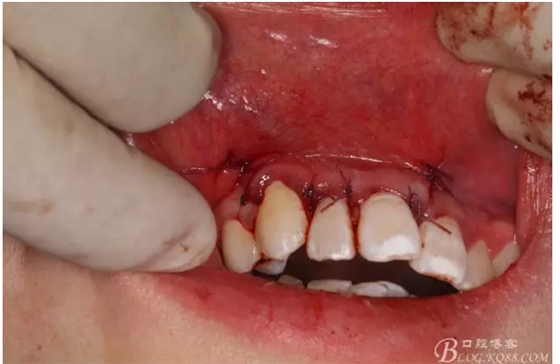

圖2.根管治療術后直接局部 麻醉下切開、翻瓣,發(fā)現(xiàn)12唇側骨壁有綠豆大小骨缺損

圖14.縫合水平切口

圖15.縫合垂直切口

圖16.縫合完畢,一周拆線。